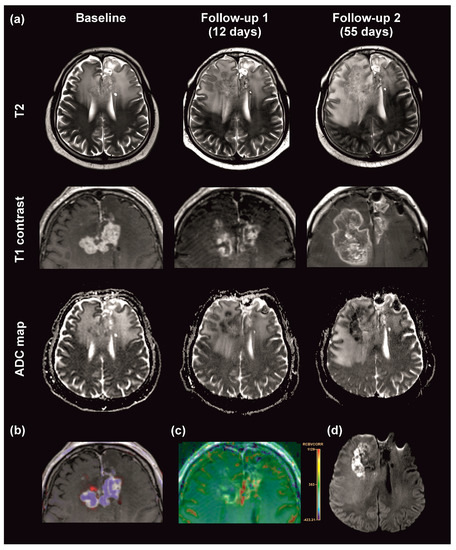

3.3. MRI Growth Patterns under Regorafenib Treatment

3.4. Cerebral Diffusion Weighted Imaging Lesions in Regorafenib-Treated Patients